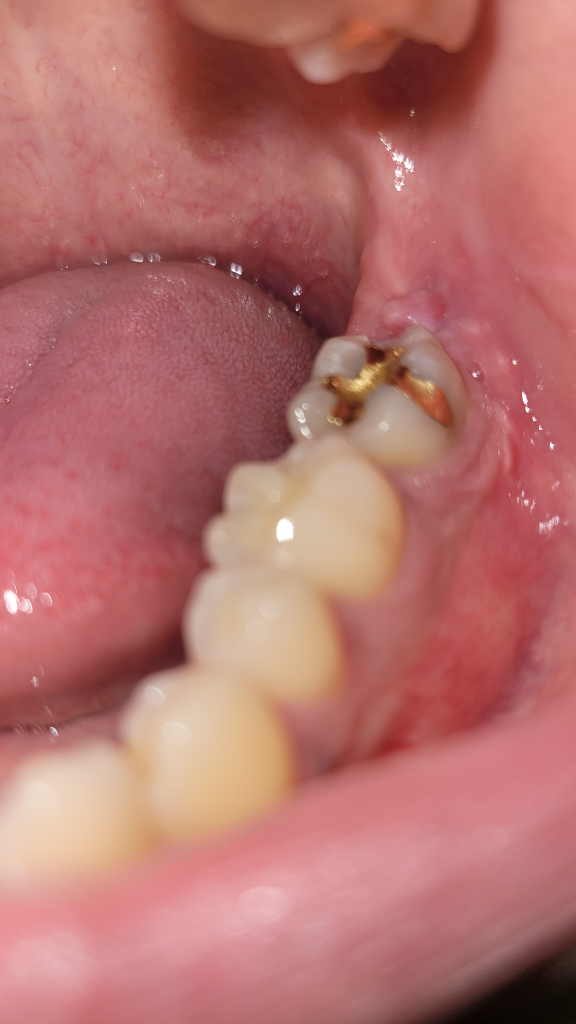

발치한 부위에 대한 다시 한번 평가를 받아보셔야 할 것 같습니다. 단순히 부서진 뿌리 부분을 놔두고 봉합했다고 해서 나타나는 증상은 아닌 것으로 보이며 잇몸이 현재 정상적인 회복이 아닐 수도 있어 보입니다. 사진만으로는 판단이 어렵고 방사선 사진 등의 다각도적인 사진이 필요합니다. 현재 상태에는 가까운 치과 방문 후 검사를 한 번 받아보는 것을 권해드립니다.

잇몸이 회복하는 과정에서 과증식 된 것으로 보이며 크게 문제가 될 것으로 보이지는 않습니다.

잇몸이 과증식되서 그런겁니다. 크게 문제가 되진 않지만, 불편하시다면 치과에 가셔서 마취후 저부위만 제거 하시면됩니다.

사랑니를 발치하고 난뒤에 잇몸은 초반에는 울퉁불퉁 할수 있습니다.

하지만 시간이 지나면서 점차 원래의 상태로 돌아오는 경우가 많아요.

발치부위를 자극하지 마시고 어느정도 아물게 되는 2주 동안에는 무리한 운동을 하지 않는것이 좋습니다.